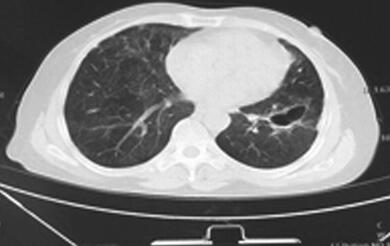

入院后检查:生命体征尚平稳,急性病容,呼吸急促,有发热,体温38.6℃,双肺散在湿性啰音。心律齐,心率快,114次/分,各瓣膜听诊区未闻及杂音,腹部无明显阳性体征,双下肢无水肿。脑膜刺激征阴性,病理征未引出。血常规:WBC 18.3×109/L,N% 94.1%,HGB 108g/L,PLT 130×109/L。红细胞沉降率:96mm/h。PCT 18.7ng/ml,BNP 15 200pg/ml,肝肾功能未见明显异常。低钠血症,低钾血症,结核菌素试验(+)。3次痰抗酸染色未见抗酸杆菌。3次痰培养未发现致病菌。血气分析(吸氧2L/M)提示:pH 7.492,PaO2 59.3mmHg,PaCO2 16.3mmHg。抗核抗体(ANA)、ANA谱、dsDNA抗体及抗中性粒细胞抗体均正常。钩端螺旋体抗体、恙虫病抗体、流行性出血热抗体均阴性。真菌D-葡聚糖+曲霉菌半乳甘露聚糖抗原:均正常。HAV+HIV+HCV+TPPA抗体:均正常。呼吸道感染病原体IgM抗体:呼吸道合胞病毒-IgM抗体阳性(+),余均阴性。(2014年6月29日)肺部CT平扫(图1):):①双肺弥漫性病变伴空洞形成,肺炎并脓肿?肉芽肿性病变?②左下肺脓肿形成。

图1 2014年6月29日胸部HRCT

双肺弥漫性病变伴空洞形成,左下肺脓肿形成